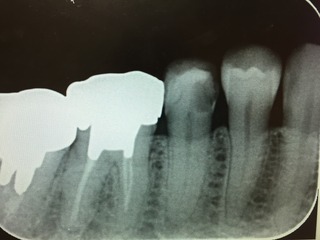

ドッグベストセメント

歯の神経近くまでの虫歯に有効なドッグベストセメントを利用しています。

虫歯があれば今まではその部分を削りとってその部分に他の材料を詰めていました。虫歯を完全に取り除くと場合によっては歯髄までとることになります。この セメントは虫歯の部分を取り除かずにその上から詰めることで虫歯菌を死滅させて正常に戻すことができます。 すなわち歯をほどんど削らずに虫歯を治すことができるのです。